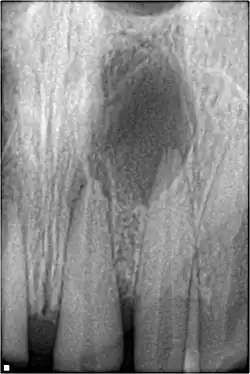

Pulpal necrosis

Pulp necrosis usually occurs either as ischaemic necrosis (infarction) caused by disruption to the blood supply at the apical foramen or as an infection-related liquefactive necrosis following dental trauma (2). Signs of pulpal necrosis include[42]

- Persistent grey colour to tooth that does not fade

- Radiographic signs of periapical inflammation

- Clinical signs of infection: tenderness, sinus, suppuration, swelling

Treatment options will be extraction for the primary tooth. For the permanent tooth, endodontic treatment can be considered.